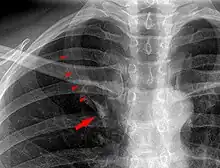

In human anatomy, an azygos lobe is a normal anatomical variation of the upper lobe of the right lung.[1] It is seen in 0.3% of the population.[2] Embryologically, it arises from an anomalous lateral course of the azygos vein,[3] in a pleural septum within the apical segment of the right upper lobe or in other words an azygos lobe is formed when the right posterior cardinal vein, one of the precursors of the azygos vein, fails to migrate over the apex of the lung and penetrates it instead, carrying along two pleural layers as the azygous fissure, that invaginates into the upper portion of the right upper lobe.[1]

An azygos lobe is usually an incidental finding on chest x-ray or CT scan. It is asymptomatic and not associated with any morbidity.[4][5] However, it can cause technical problems in thoracoscopic procedures.[6] The presence of the azygos lobe could alter the normal location of the superior vena cava or may be associated with other anomalies, including esophageal atresia or intrapulmonary right brachiocephalic veins.[7]